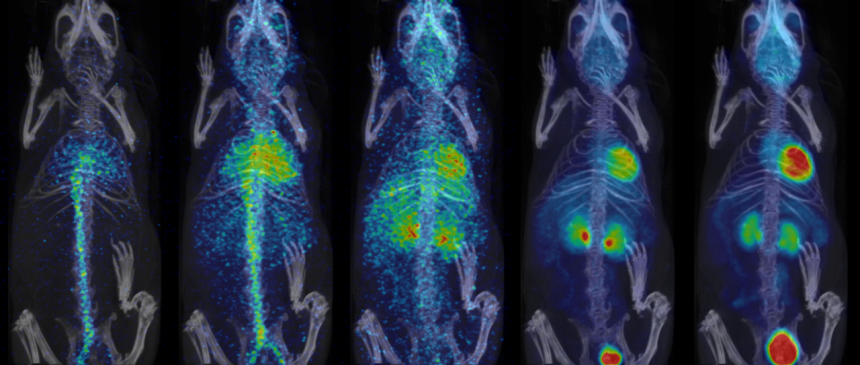

- Fully automated PET/CT stitched protocol, including attenuation correction (AC) map for rats up to 250 mm in length

Fast extended PET/CT imaging for full rat body coverage. Image Credit: Bruker BioSpin Group

Dynamic 18FDG/PET scan in healthy mouse acquired in LM, reconstructed with variable intervals and displaying myocardium and blood. Image Credit: Bruker BioSpin Group